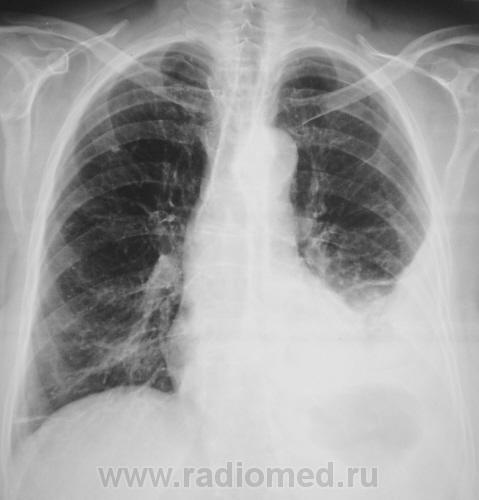

Пациент направлен на исследование ОГК с диагнозом "Пневмония".

Ну вот, всем все ясно. Мне ничего не ясно. Кроме того, что у пациента частично осумкованный гидроторакс.

Добрый вечер, Валентин Львович! Я пока тоже кроме осумкованного плеврита и небольшого объемного уменьшения базальных сегментов левого легкого с уверенностью ничего не вижу. Можно поинтересоваться, чем обусловлена тяжесть состояния пациентки, клинической картиной? Какие жалобы гастроэнтерологической группы она предъявляет?

Пациентка направлена на рентгенографию ОГК с диагнозом пневмония. Лечилась "на дому", на участке, пользовал врач общей практики. Жалобы на кашель, высокую температуру, слабость, ну и другие "грудные жалобы". Жалоб "гастроэнтерологической группы", не предъявляет. Пациентка пожилая. Вот, все в "купе", и обусловило "общее тяжелое состояние".

Ну, надо полагать, что здесь пневмония, осумкованный плеврит. А вот где полость? Абсцесс? Эмпиема плевры?